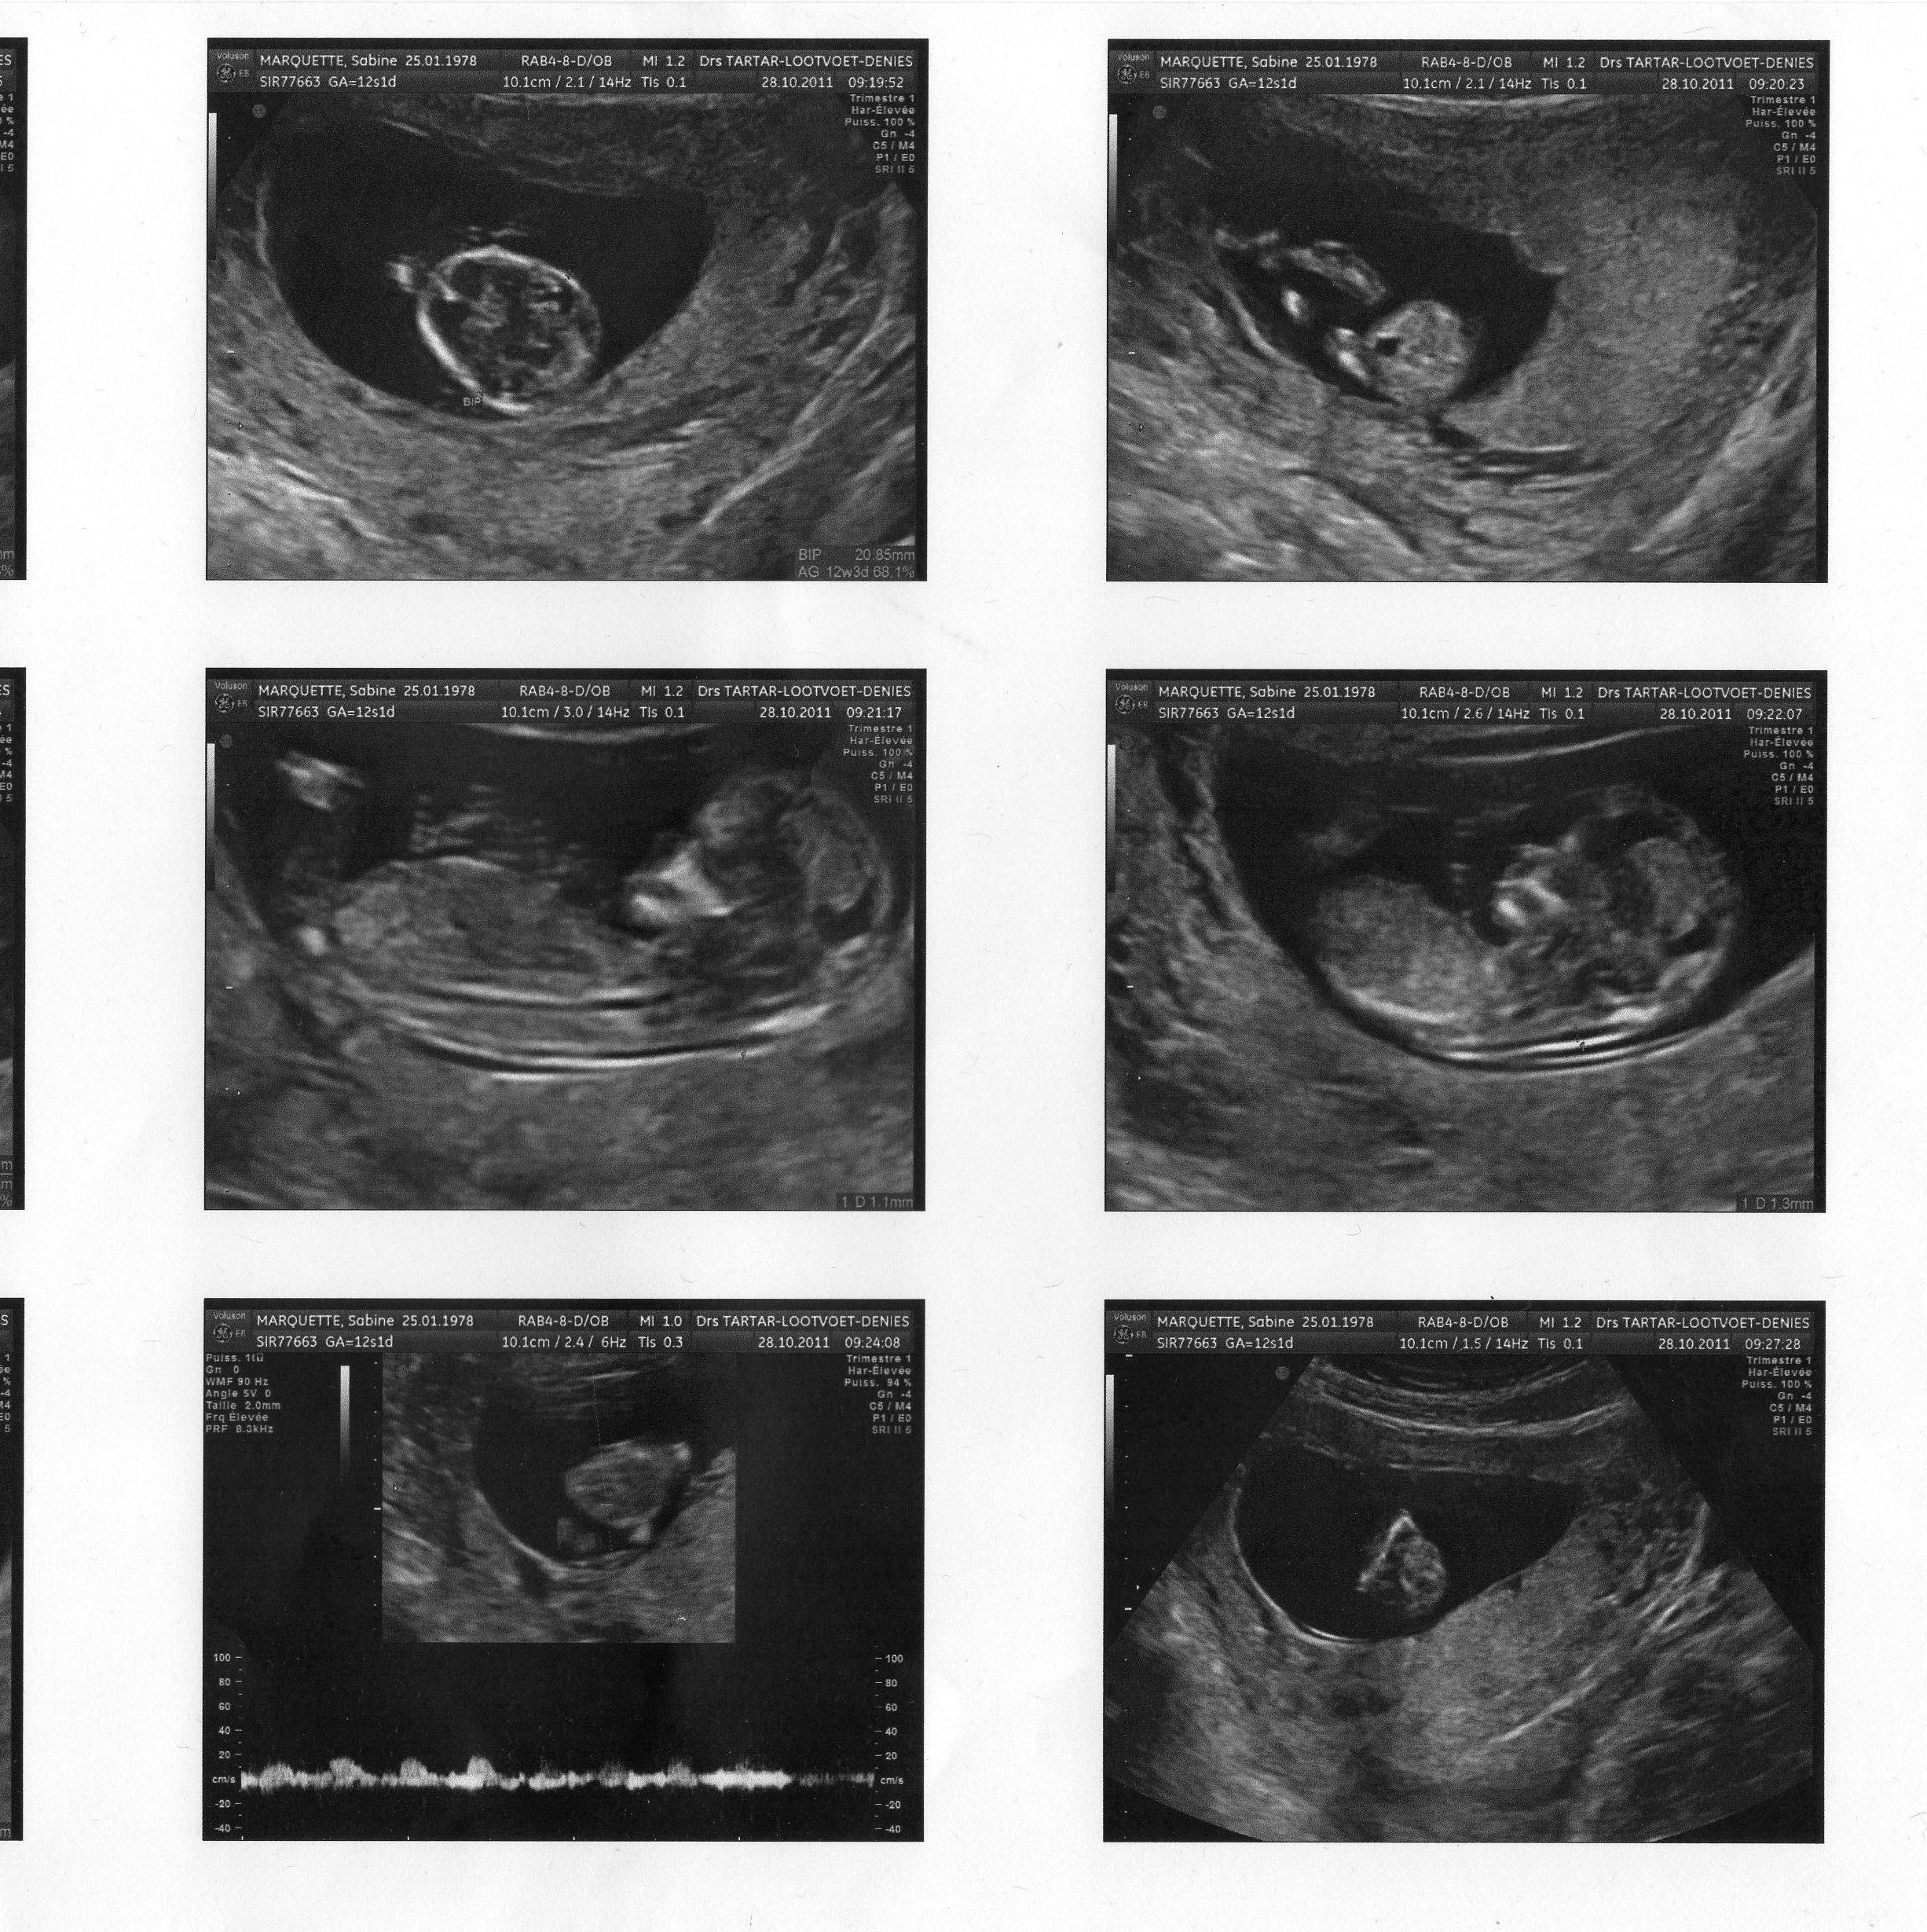

Comment savoir le sex du bébé à 3 mois?Comment savoir la position de bébé sans Echographie?Analyser son échographie pour connaître le sexe de bébé Il vous faut donc passer l'échographie T1 (entre 11 et 13 semaines d'aménorrhée) pour avoir des éléments de réponse C'est généralement un grand moment dans votre calendrier de grossesse, émouvant pour les parents, car le fœtus commence à ressembler à un bébé

Savoir le sex du bebe echographie-Échographies Le moyen le plus fiable de connaître le sexe du bébé est l'échographie"La première échographie se déroule au cours du troisième mois de grossesse entre la 11e et la 13e semaines d'aménorrhéeDans certains cas, le sexe du bébé peutêtre annoncé lors de ce premier examen", explique le Dr Philippe Mironneau, gynécologue etJ'ai toujours demandé le sexe de mes bébés à l'échographie de migrossesse J'y voyais l'occasion de choisir un prénom, de personnaliser mon lien avec « ma poulette » plutôt que « le bébé » et de préparer l'arrivée du nourrisson, en achetant

L'échographie du 2e trimestre permet de découvrir le sexe de votre bébé Saurezvous reconnaître s'il s'agit d'une fille ou d'un garçon ?Pour toutes celles qui se posent des questions sur le"bourgeon" et qui ne savent pas patienter, voila des images vous permettant de comprendre la formation du sexe du foetus et ainsi déterminer le sexe des l'écho des 12 semaines Je vous met les images ainsi qu'une série de liens!Pour connaître le sexe du bébé, le moyen le plus fiable reste l'échographie pratiquée entre les semaines 18 et de la grossesse La procédure d'imagerie doit pouvoir indiquer avec une précision de 80% à 90% si tu attends une fille ou un garçon